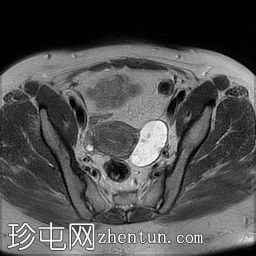

轴位

DWI

左侧卵巢增大,呈弥漫性低T1信号和高T2信号,可见周边卵泡,部分卵泡除周边卵泡周围有环状强化外,无明显实质强化。左侧附件蒂呈漩涡状,提示卵巢扭转。